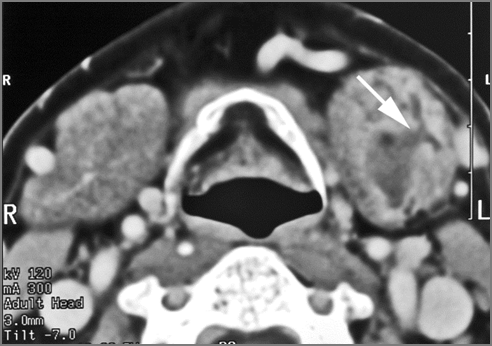

There is abscess at the periphery of the lymphoid tissue of the palatine tonsil within the potential peritonsillar space of the palatine tonsil within the potential peritonsillar space

[Yes/No]

There is edema/abscess within the fat of the adjacent parapharyngeal and retropharyngeal spaces. [Yes/No]

Tonsillitis [with/without] tonsillar abscess.

Tonsillitis [with/without] peritonsillar abscess.